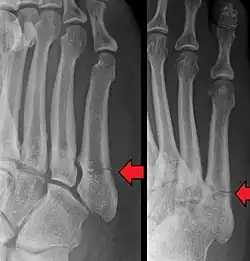

Differential diagnosis

- Proximal diaphysis, typically stress fracture.[12][13]

- Metaphysis: Jones fracture[14]

-Tuberosity: Pseudo-Jones fracture[15] (avulsion fracture).[15]

Other proximal fifth metatarsal fractures exist, although they are not as problematic as a Jones fracture. If the fracture enters the intermetatarsal joint, it is a Jones fracture. If, however, it enters the tarsometatarsal joint, then it is likely an avulsion fracture caused by pull from the fibularis brevis tendon. An avulsion fracture at the base of the fifth metatarsal is sometimes called a "dancer's fracture" or a "pseudo Jones fracture", and usually responds readily to non-operative treatment.[18] The X-ray appearance of the developmental "apophysis" in this area may have some resemblance of a fracture, but is not a fracture; it is the secondary ossification center of the metatarsal bone. It is a normal finding that occurs at this site in adolescents.[19] If an injury to that area has occurred, the physician is often able to interpret certain radiographic clues to make the differentiation. An avulsion fracture at this location is typically extra-articular and oriented transversally as compared to the longitudinal orientation of an unfused apophysis.[19]